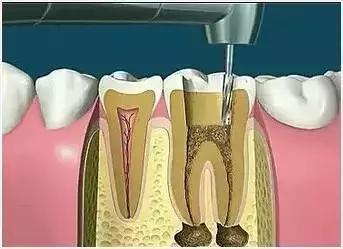

去净腐质和原有充填物、揭净髓顶,看到整个髓底解剖结构以便后续治疗顺利进行。

根管清理成形的目的是去净根管壁上的感染物,通过根管器械的切削作用去除感染的牙本质并清理根管壁细菌以利于根管充填。

根管冲洗的目的是清除微生物、冲掉残渣,润滑根管器械和溶解有机残渣。然后,再进行根管消毒,使根管内达到无菌状态。